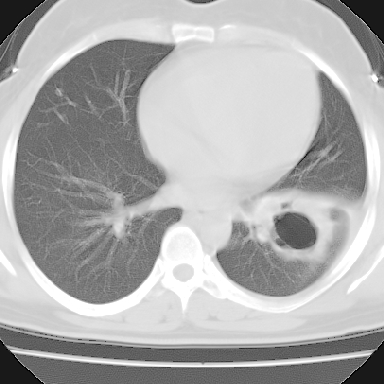

f 37 咳嗽1周,咯血1次,无浓痰,无明显发热

左下肺肿块影,内可以见小泡征,并见厚壁空洞形成,洞内缘凹凸不平,可见壁结节。靠近胸膜侧可见胸膜凹陷征。左侧胸腔内可见少量低密度积液影。右肺可见两处高致密的小结节影。

考虑:左下肺周围型肺癌伴右肺转移